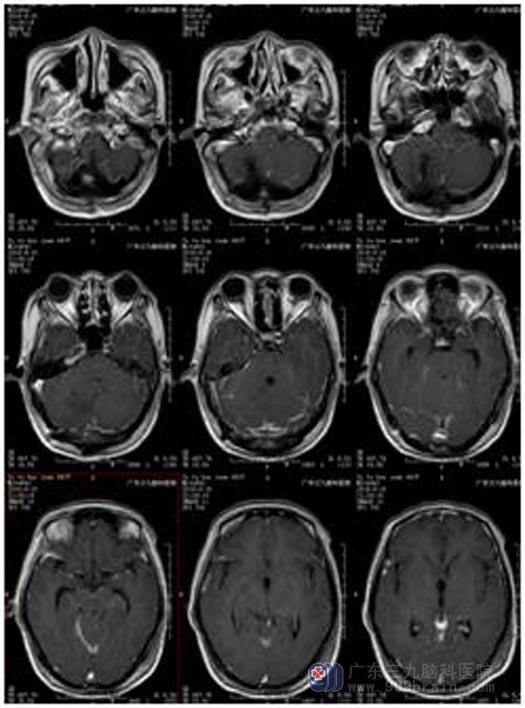

为找出原因,家人带着惠姨来到广东三九脑科医院综合神经外科。CT检查结果显示:右侧小脑半球存在5.5cm×3.6cm×3.0占位性病变,小脑扁桃体下疝形成,幕上梗阻性脑积水,初步诊断1.右侧小脑半球囊实质性病变:考虑血管母细胞瘤,2.脑积水。

鲁明主任告诉他们:小脑扁桃体下疝患者常常会出现眩晕,耳鸣复视,走路不稳及肌无力,一旦明确诊断,并且情况严重,应尽快手术治疗。完善各项检查,由鲁明主任主刀在全麻下行右侧小脑占位切除术。手术过程顺利,肿瘤完整切除。术后惠姨神志清醒,正在进一步的康复治疗中。